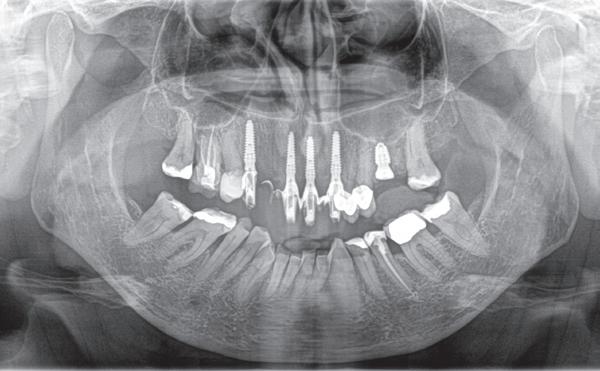

Op basis van de eerste indruk die ik krijg tijdens het globale klinische onderzoek, wordt een orthopantamogram (zie OPT bij intake) gemaakt. Samen met de meegestuurde röntgenopnames (zie solo’s) wordt eenvoudig vastgesteld dat er sprake is van ernstig botverlies, bijvoorbeeld bij de 16, 17 en de 18 tot 100% verlies aan alveolair bot. De 16 vertoont daarnaast een grote peri-apicale laesie. In het eerste kwadrant lijkt daarom alleen de 12 een goede prognose te hebben. De 12 vormt samen met de 16 een vierdelige brug en deze constructie lijkt dus verloren. Overigens vermoed ik dat de 12 eigenlijk een cuspidaat is en ontbreekt de 12 (agenesie). Daarnaast worden sterk verdiepte ontstoken pockets geconstateerd bij de 16, 17 tot 12 mm en zijn de elementen sterk verhoogd mobiel. De 11 lijkt als enige element van de gehele dentitie niet te zijn behandeld.

5. Implantaten geplaatst op geleide van een boorsjabloon; botopbouw met sinuslift volgens de GBR-techniek en Caldwell Luc methode; materialen: Oragraft & BioOss, Ossix membr, hyaluronzuur. In de BK is gekozen voor Bego implantaten (Bego SC en RSX 3,75x 11,5 & 13mm).

Tijdens de chirurgische behandeling worden na het afschuiven van de flap de posities bepaald van de implantaten met de boorsjabloon. In de bovenkaak worden 7 implantaten geplaatst en in de onderkaak 8

implantaten geplaatst terwijl in de zijdelingse delen voor een bredere diameter (3,75 & 4,1) is gekozen, met lengte 8,5 en 10mm.

7. OPT na abutmentchirurgie 6 maanden later. De integratie van de implantaten met de botopbouw & sinusliften verloopt voorspoedig.